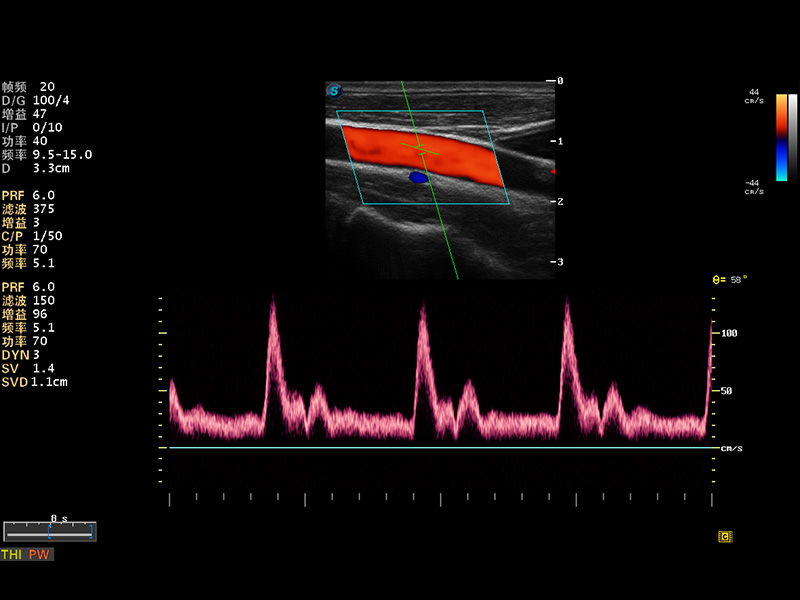

S8 EXP便携式彩色多普勒超声诊断仪是美狮贵宾会官网研发的高端全身应用型便携彩超。高通道的VIS平台融合可视化(Visual)、智能化(Intelligent)和人性化(Smart)的特点,配以美狮贵宾会官网自主研发生产的探头大家族,使您能够快速、准确的获得病人信息,提高工作效率的同时减轻疲劳。

成像技术

多波束形成器